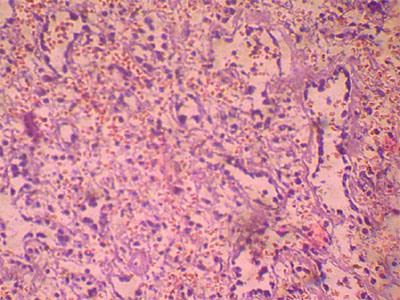

Гломерулонефритом являются иммуновоспалительные заболевания с преимущественным поражением клубочков, а также с вовлечением канальцев и межуточной (интерстициальной) ткани. Гломерулонефрит по механизму развития относится к группе инфекционно-аллергических заболеваний. Термин «инфекционно-аллергический» отражает формирование инфекционной аллергии в сочетании с различными неиммунными повреждениями органа. Существуют и аутоиммунные формы заболевания, которые обусловлены повреждением почечной ткани аутоантителами, т. е. антителами к собственному органу.